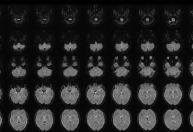

Engenheiros do Centro Universitário FEI e pediatras da Unifesp (Universidade Federal de São Paulo) desenvolveram em parceria uma ferramenta de inteligência artificial capaz de identificar o nível de dor de recém-nascidos internados em UTIs (Unidades de Terapia Intensiva). A tecnologia usa modelos multimodais de linguagem e visão (vision-language models), que integram imagens e textos para interpretar expressões faciais dos bebês com mais precisão e menos subjetividade.

A pesquisa, financiada pela Fapesp, foi publicada na revista Pediatric Research e demonstrou que o sistema de inteligência artificial supera técnicas tradicionais de deep learning na identificação de estados de dor e conforto. Além disso, o modelo não precisa ser treinado separadamente para cada tarefa, o que amplia sua aplicabilidade clínica.